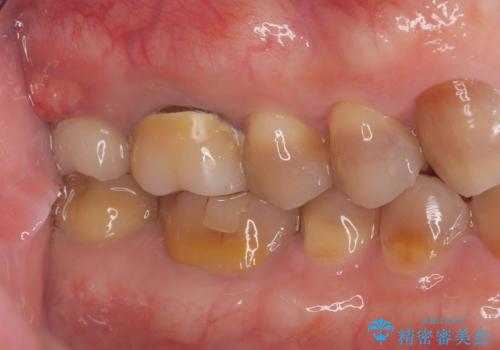

- 484,000円(インプラント手術と被せ物の費用全て込み)インプラント10年保障費用は治療当時の料金となります

抜歯と歯根嚢胞の除去を行った後、インプラントで治療しました。治療後は「自分の歯のように咬める」と大変ご満足いただけました。